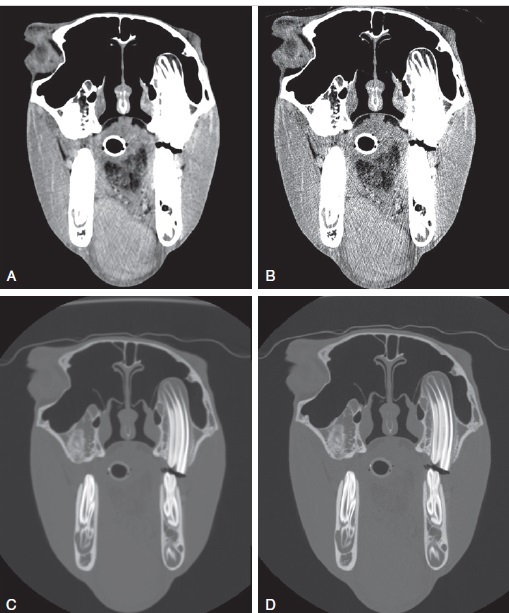

Figure 71-2. The same CT image of a horse with an intermandibular soft tissue sarcoma, but reconstructed with different algorithms and displayed with different window/level settings. (A) Transverse image reconstructed with a soft tissue algorithm, and displayed with a soft tissue window/level. (B) Transverse image of the same horse, reconstructed with a bone algorithm, and displayed with a soft tissue window/level. Note that the image in (A) has a smoother appearance to the soft tissues with less graininess as the soft tissue algorithm reduces noise. (C) Transverse image reconstructed with a soft tissue algorithm and displayed with a bone window/level. (D) Transverse image reconstructed with a bone algorithm and displayed with a bone window/level. Note that the image in (C) has a more blurred appearance compared with (D), with decreased spatial resolution and detail of bony structures.